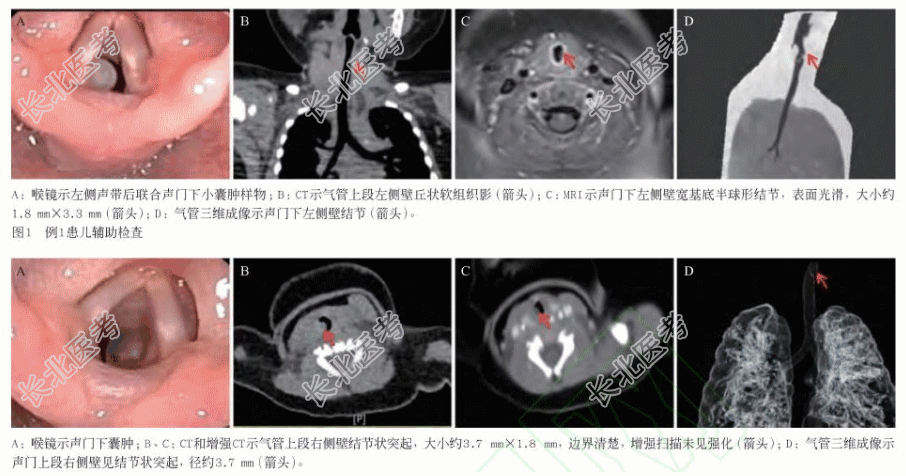

- [材料题] 患儿男性,5月龄,因“胎龄24+6周,早产后呼吸费力25min”入院新生儿科,出生体质量770g。入院后完善胸部CT及喉镜后发现气管右侧上壁结节,现纠正胎龄43+6周,体质量4530g,在高流量鼻导管给氧下(FI0230%,FLOW3L/min)呼吸稍费力,血氧饱和度维持尚可,请求我科会诊,考虑声门下良性肿瘤可能,建议手术切除治疗。患儿合并支气管肺发育不良、先天性心脏病:房间隔缺损、动脉导管未闭、肺动脉高压,既往气管插管史。查体:面色尚红润,三凹征(-),双肺呼吸音稍粗,未及啰音。辅助检查:喉镜示声门下新生物,囊肿可能(图A),CT和增强CT示气管上段右侧壁结节,考虑良性病变,囊肿可能(图B、图C),气管三维成像示气管上段右壁见结节状突起,径约3.7mm(图D)。手术治疗:行支撑喉镜下声门下肿物切除术,术中见双侧声带表面光滑,活动良好,声门下右侧气管内见球型囊肿样新生物,肿物表面光滑,伴血管,予以完整切除,无气道活动性出血。术后病理:送检组织囊壁样,镜下见囊壁衬覆呼吸道上皮,囊壁内可见浆液黏液性腺体,提示支气管源性囊肿(符合BC)。